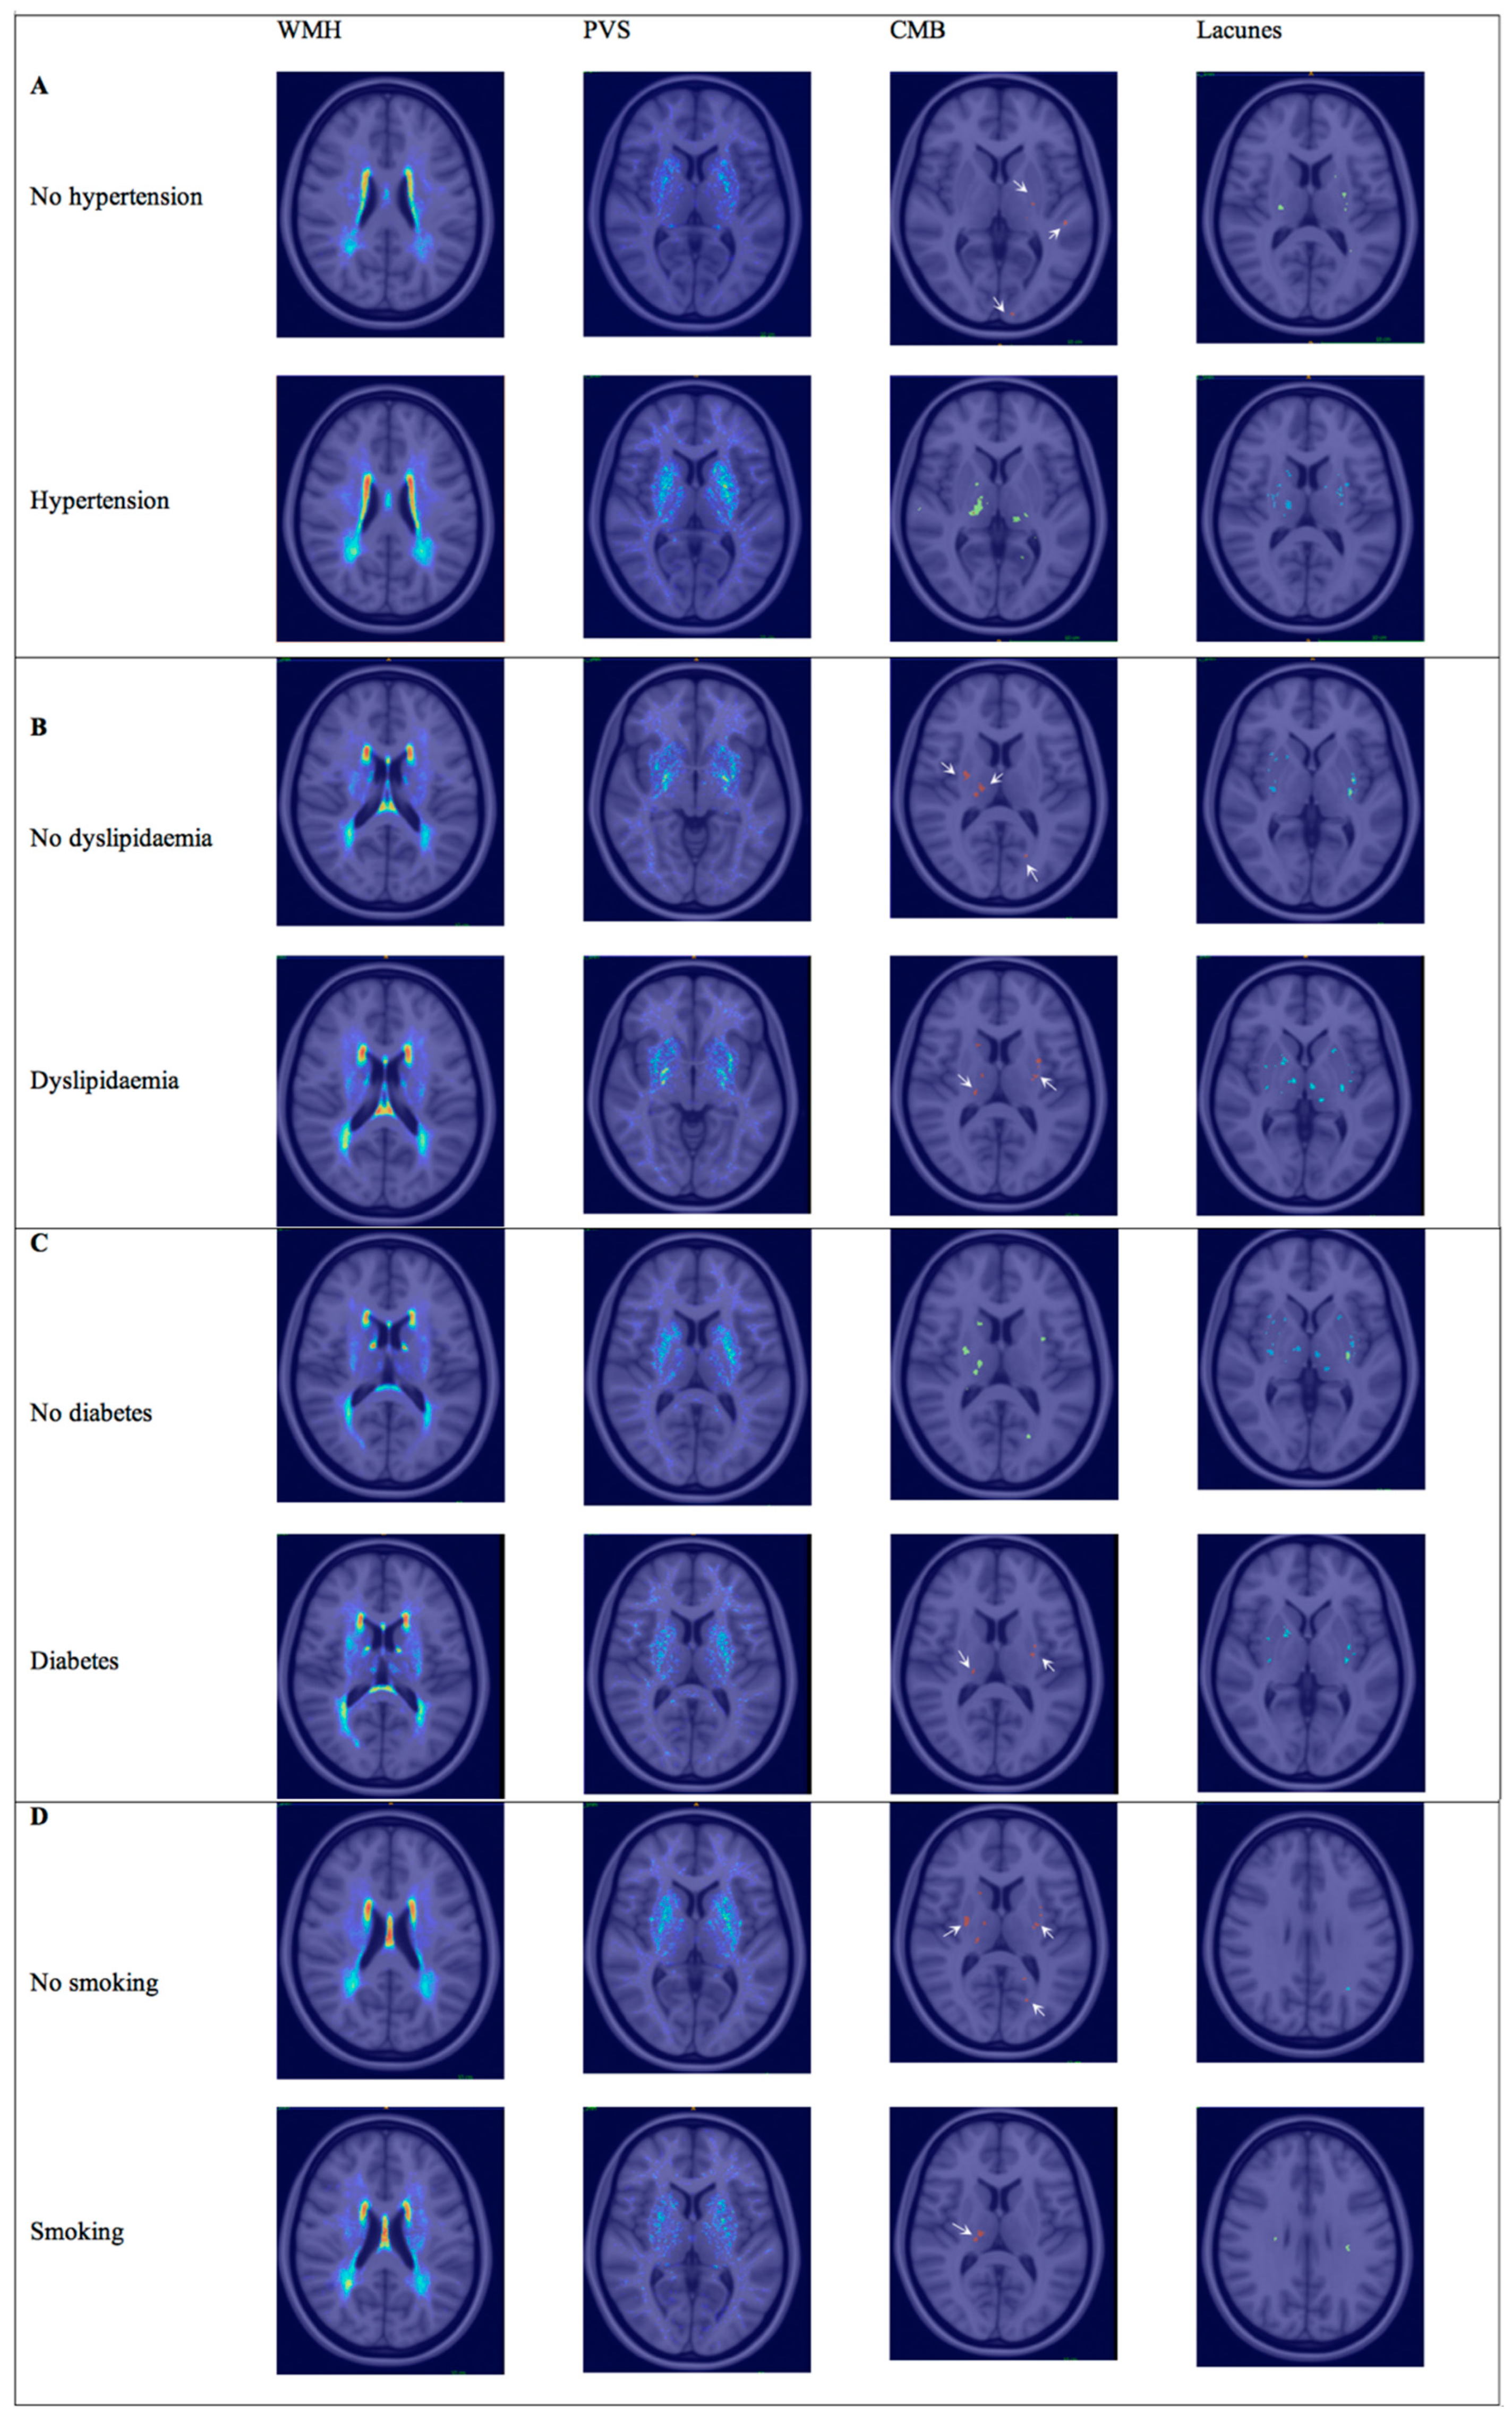

3.1. Hypertension

3.2. Hyperlipidemia

3.3. Diabetes

3.4. Smoking